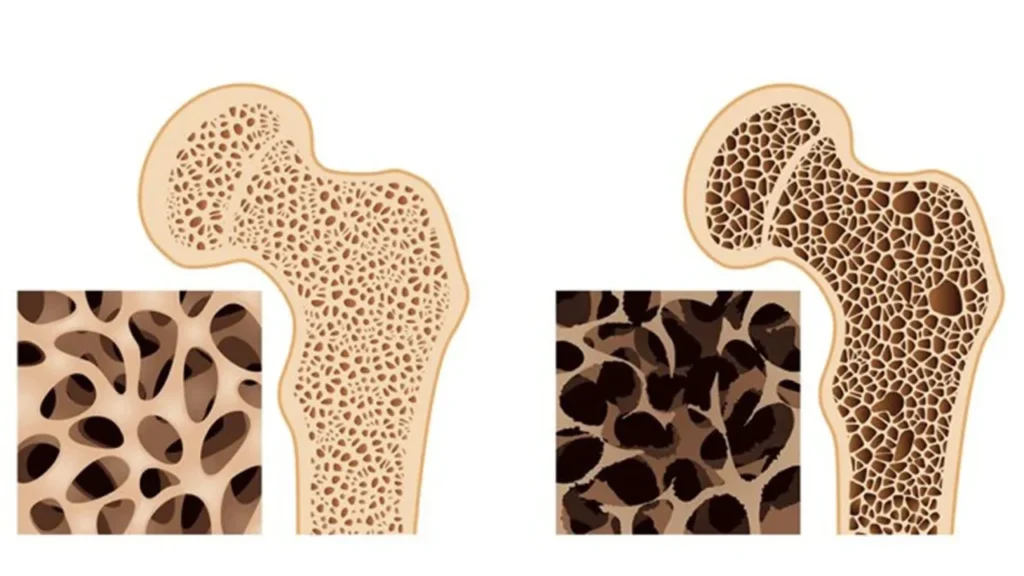

Prevenção, diagnóstico e tratamento para fortalecer os ossos e reduzir o risco de fraturas.